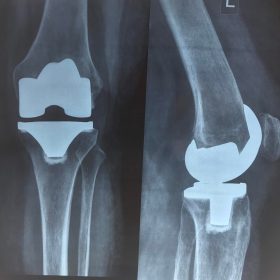

Παρόλα αυτά στην πλειονότητα των περιπτώσεων, με την πάροδο του χρόνου οι παραπάνω τρόποι αντιμετώπισης καθίστανται αναποτελεσματικοί. Η ένταση του πόνου και ο αντίκτυπος στην καθημερινότητα γίνονται αφόρητα.

Σε αυτό το σημείο η Αρθροπλαστική Γονάτου αποτελεί μονόδρομο.